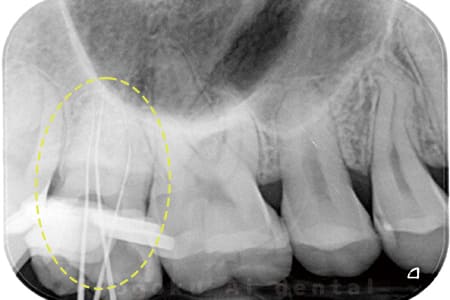

根管内の異物

- 原因

- 根管内異物(ファイル破折)による慢性根尖性歯周炎

- 治療期間

- 3ヶ月

- 治療内容

- マイクロスコープを使用した根管内異物除去並びにマイクロエンド

- 治療費用

- 121,000円(ファイル除去費用も込み)

他院で細い器具(ファイル)が根管内に破折した状態で、咬合痛を主訴に来院された患者様です。ファイルをマイクロスコープ下で除去し、根管治療を行ないました。